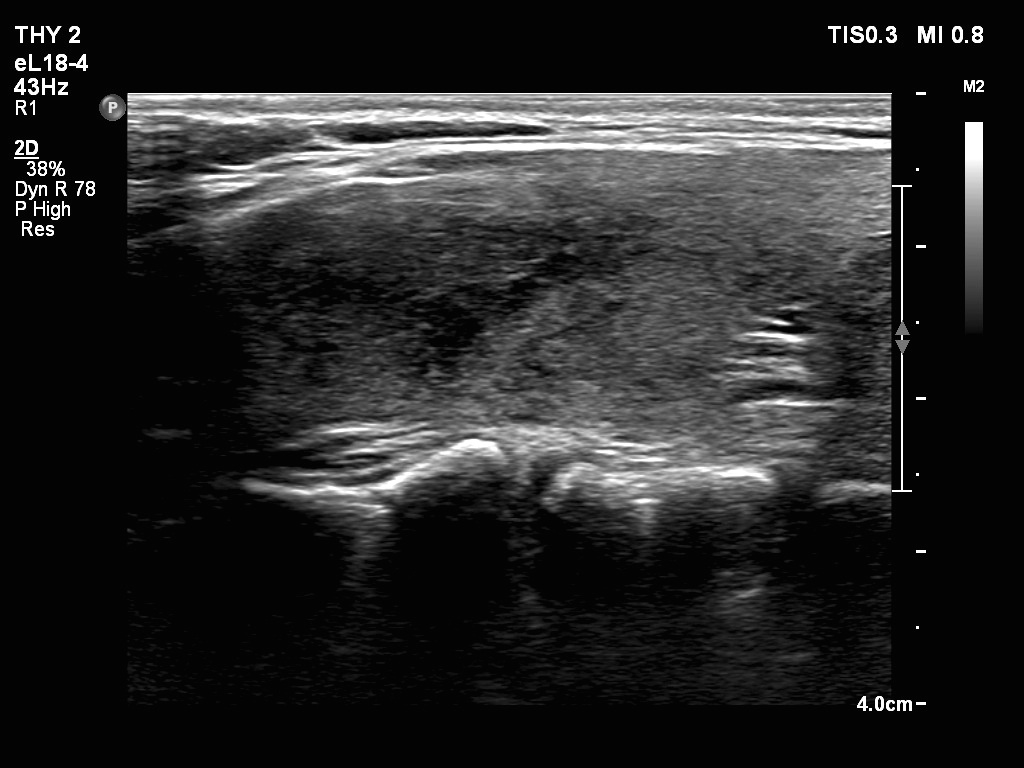

Ultrasonography. The thyroid was echonormal. There were two nodules in the right lobe. The upper was hyperechogenic-cystic while the lower was a minimally-moderately hypoechogenic. The latter had irregular, lobulated margins. There was a hypoechoic area in the upper two-third of left lobe. The discrete area presented ill-defined margins and decreased vascularization. A spongiform cyst was found in the lower pole of the left lobe.